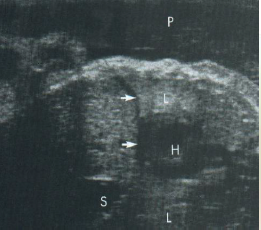

What are the sonographic finding of the diaphragm?

what plane was this image taken in?

Hypoechoic compared to lung

Between lung/liver/spleen

Seen consistently after 20 weeks gestation

Note this longitudinal view of the thorax and abdomen & is early in the gestational age - the lungs are still hypoechoic compared to the liver

what plane was this scanned in?

how far along is this GA? Why?

Note this longitudinal view of the thorax & abdomen that is later in the gestational age - the lungs are now hyperechoic compared to the liver